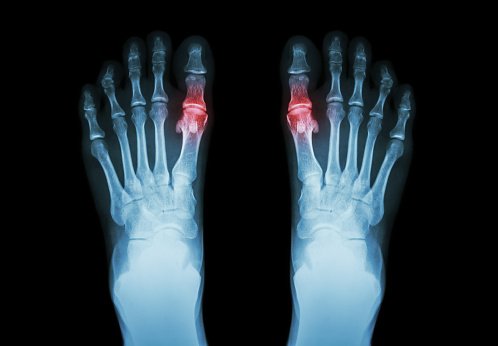

Diagnóstico y tratamiento de la hiperuricemia y la gota: revisión sistemática de las guías de práctica clínica y las declaraciones de consenso.

BMJ Open 2019Se necesitan mejoras en la calidad metodológica  de los documentos de orientación sobre gota e hiperuricemia. Falta evidencia para ciertas preguntas clínicas, a pesar de numerosos ensayos en este campo. Promover métodos de desarrollo de orientación estándar y sintetizar evidencia clínica de alta calidad son enfoques potenciales para reducir las inconsistencias de recomendación.